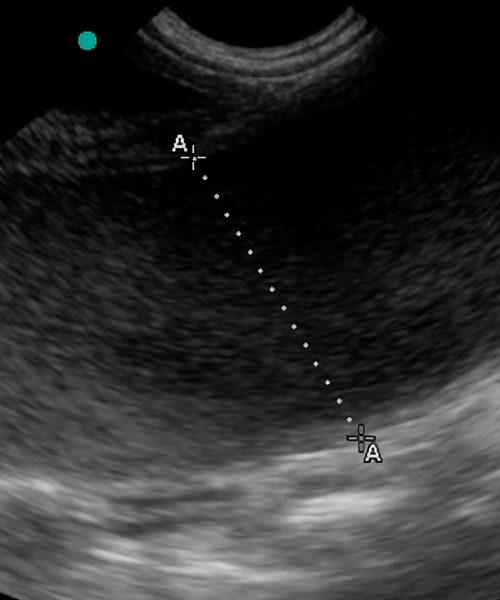

Ofrezco especialización en ecografía veterinaria y una colaboración integral basada en vuestro historial clínico.

Valido la precisión diagnóstica comparando las imágenes ecográficas con los hallazgos quirúrgicos reales.

Garantizo transparencia y confianza exhibiendo en este apartado casos reales con su correlación intraoperatoria documentada.